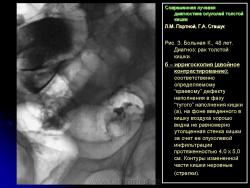

2. Краевой “дефект” наполнения более выражен при дозированной компрессии этого участка кишки – симптом, который может отражать изъязвление в инфильтративно измененном участке стенки кишки (рис. 3).

2. Краевой “дефект” наполнения более выражен при дозированной компрессии этого участка кишки – симптом, который может отражать изъязвление в инфильтративно измененном участке стенки кишки (рис. 3).

2. Краевой “дефект” наполнения более выражен при дозированной компрессии этого участка кишки – симптом, который может отражать изъязвление в инфильтративно измененном участке стенки кишки (рис. 3).